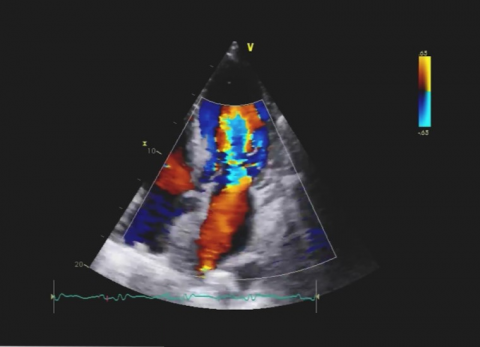

Wideo Echokardiografia. Przypadek 31

dr hab. n. med. prof. UJ Andrzej GackowskiPacjent z narastająca dusznością z podejrzeniem niedomykalności aortalnej.